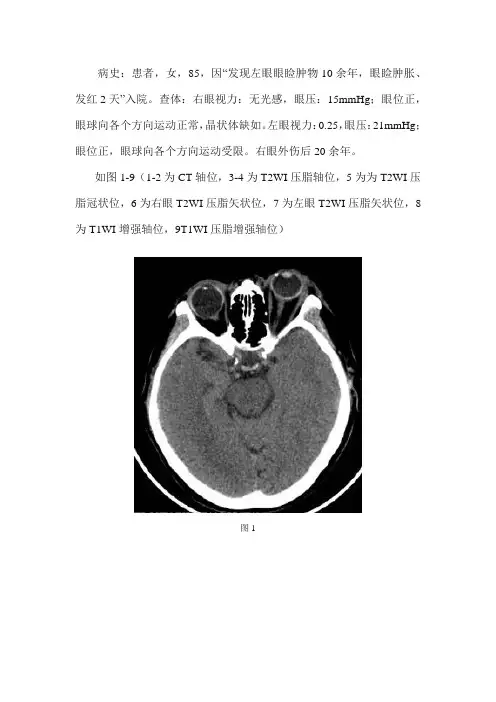

病史:患者,女,85,因“发现左眼眼睑肿物10余年,眼睑肿胀、发红2天”入院。

查体:右眼视力:无光感,眼压:15mmHg;眼位正,眼球向各个方向运动正常,晶状体缺如。

左眼视力:0.25,眼压:21mmHg;眼位正,眼球向各个方向运动受限。

右眼外伤后20余年。

如图1-9(1-2为CT轴位,3-4为T2WI压脂轴位,5为为T2WI压脂冠状位,6为右眼T2WI压脂矢状位,7为左眼T2WI压脂矢状位,8为T1WI增强轴位,9T1WI压脂增强轴位)图1图2图3图4图5图6图7图8图9基础解剖影像:以上为眼器示意图及前外侧视角眼部结构立体示意图。

图1图2图3图4图5图6图7图8图9CT影像:左侧眼睑颞侧见小结节状样高密度影(蓝色箭头),边界清晰。

左侧眼球突出(黄色箭头),左侧眼环完整,鼻侧见结节样钙化影。

左眼晶状体未见异常。

左侧球后脂肪浑浊。

右侧眼球形态欠规整,右侧眼环完整,右侧晶状体未见正常形态显示(棕色箭头)。

影像诊断:左侧眼睑结节影,请结合眼科检查。

左侧眼部改变,建议MRI进一步检查。